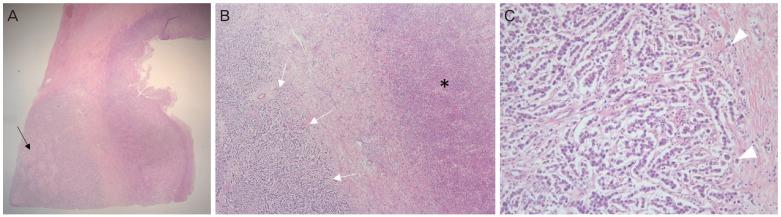

Müllerian anomalies are rare deformities in women, and only a few cases concerning gynecologic malignancies arising in patients with congenital uterine malformations have been reported. Herein, we present the case of a 34-year-old woman with dysgerminoma with a Müllerian anomaly (uterus didelphys). She had secondary amenorrhea, and an ovarian mass and uterus didelphys were discovered during examination. After right salpingo-oophorectomy, the tumor was confirmed as dysgerminoma, and a chromosome study revealed a normal female karyotype (46, XX). The patient completely responded to 6 cycles of chemotherapy. To our knowledge, this is the first reported case of dysgerminoma with uterus didelphys. Although gynecologic malignancies in patients with Müllerian anomalies are very rare, clinicians should be aware of the coexistence of gynecologic malignancies and uterine malformations.

苗勒管异常在女性中较为罕见,仅有少数关于先天性子宫畸形患者发生妇科恶性肿瘤的病例报道。在此,我们报告一例34岁患有无性细胞瘤合并苗勒管异常(双子宫)的女性病例。她出现继发性闭经,检查时发现卵巢肿块和双子宫。右侧输卵管卵巢切除术后,肿瘤被确诊为无性细胞瘤,染色体研究显示为正常女性核型(46, XX)。该患者对6个周期的化疗完全缓解。据我们所知,这是首例双子宫合并无性细胞瘤的报道病例。尽管苗勒管异常患者发生妇科恶性肿瘤非常罕见,但临床医生应意识到妇科恶性肿瘤与子宫畸形可能并存。